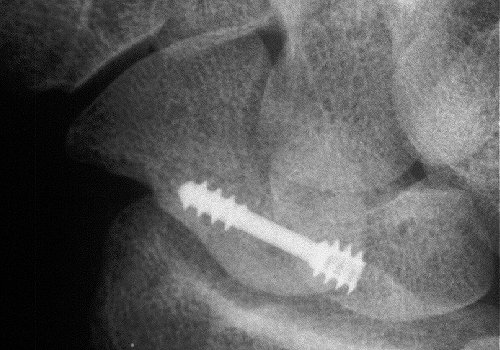

and two months postop:

Click for larger image